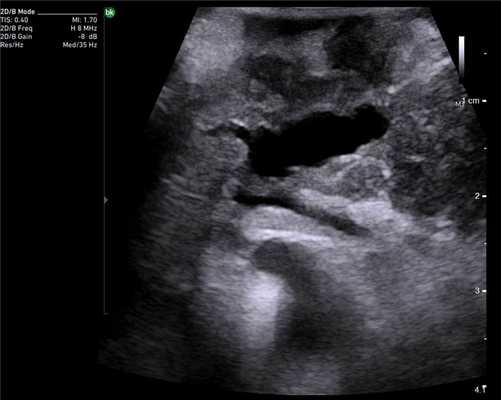

У 5 (41,7%) из 12 пациенток образования в печени имели гиперэхогенную, гомогенную структуру с четкими и ровными контурами размером от 5 до 12 мм в диаметре, которые были интерпретированы как доброкачественные образования печени — гемангиомы (табл. 2). У 4 (33,3%) пациенток образования имели анэхогенную гомогенную структуру, с четкими и ровными контурами, с гладкой внутренней выстилкой и эффектом усиления эхосигнала, размером от 3 до 11 мм в диаметре, и были интерпретированы как кисты. В 3 (25%) случаях в печени были выявлены гипоэхогенные образования солидной гетерогенной структуры с нечеткими, но ровными контурами размером от 10 мм в диаметре (рис. 1) до 22×17×15 мм в одном случае, расположенное на диафрагмальной поверхности печени, которое «самоампутировалось» в процессе исследования и при срочном гистологическом исследовании оказалось метастазом аденогенного рака (рис. 2).

Рис. 1. Эхограмма. Интраоперационное УЗИ печени (стрелкой указан метастаз рака яичника).